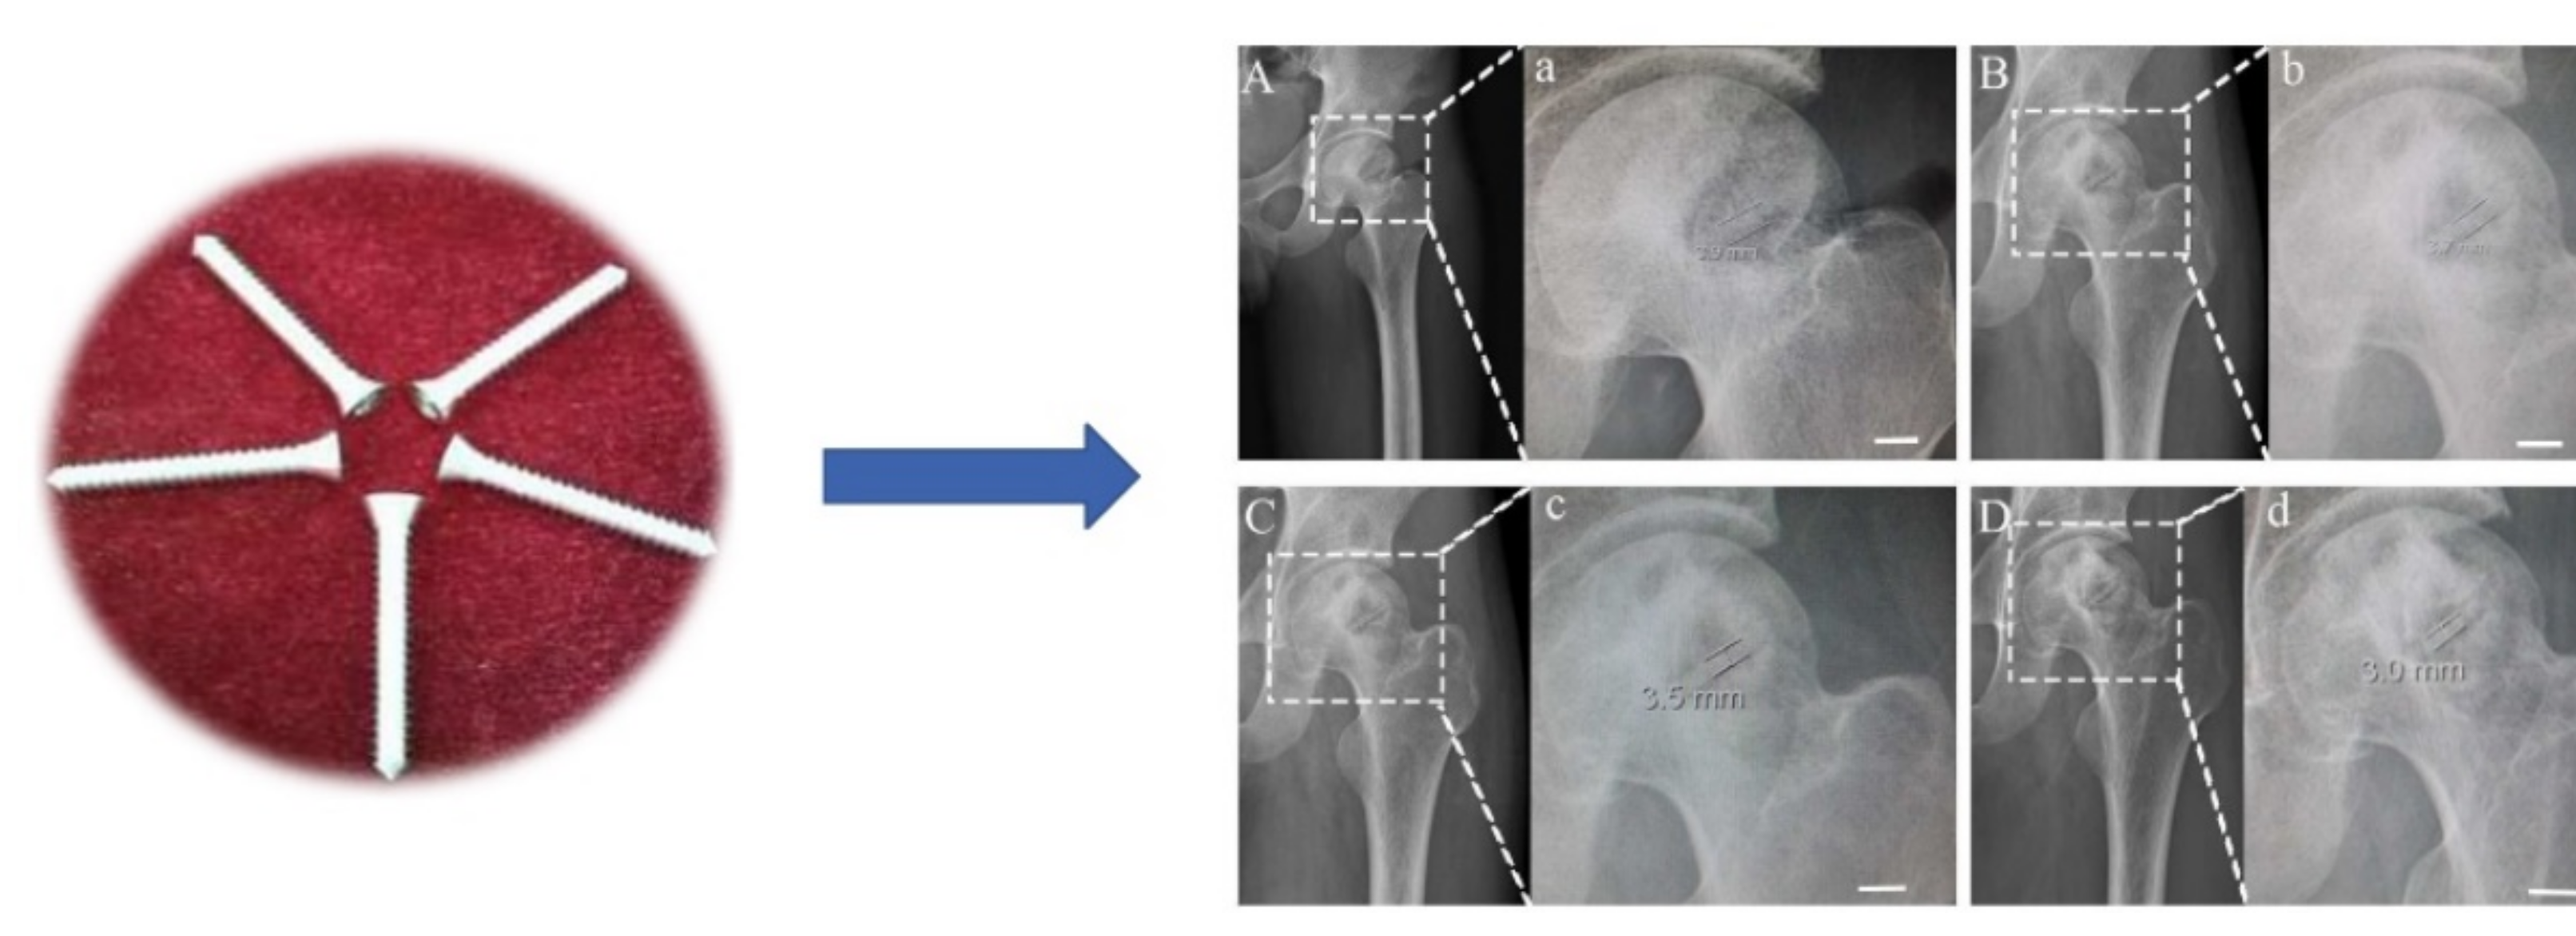

- Zhao, D.; Huang, S.; Lu, F.; Wang, B.; Yang, L.; Qin, L.; Yang, K.; Li, Y.; Li, W.; Wang, W.; et al. Vascularized Bone Grafting Fixed by Biodegradable Magnesium Screw for Treating Osteonecrosis of the Femoral Head. Biomaterials 2016, 81, 84–92. [Google Scholar] [CrossRef]

- Yu, X.; Zhao, D.; Huang, S.; Wang, B.; Zhang, X.; Wang, W.; Wei, X. Biodegradable Magnesium Screws and Vascularized Iliac Grafting for Displaced Femoral Neck Fracture in Young Adults. BMC Musculoskelet. Disord. 2015, 16, 329. [Google Scholar] [CrossRef]

- Chen, L.; Lin, Z.; Wang, M.; Huang, W.; Ke, J.; Zhao, D.; Yin, Q.; Zhang, Y. Treatment of Trauma-Induced Femoral Head Necrosis with Biodegradable Pure Mg Screw-Fixed Pedicle Iliac Bone Flap. J. Orthop. Transl. 2019, 17, 133–137. [Google Scholar] [CrossRef]

- Huang, S.; Wang, B.; Zhang, X.; Lu, F.; Wang, Z.; Tian, S.; Li, D.; Yang, J.; Cao, F.; Cheng, L.; et al. High-Purity Weight-Bearing Magnesium Screw: Translational Application in the Healing of Femoral Neck Fracture. Biomaterials 2020, 238, 119829. [Google Scholar] [CrossRef]